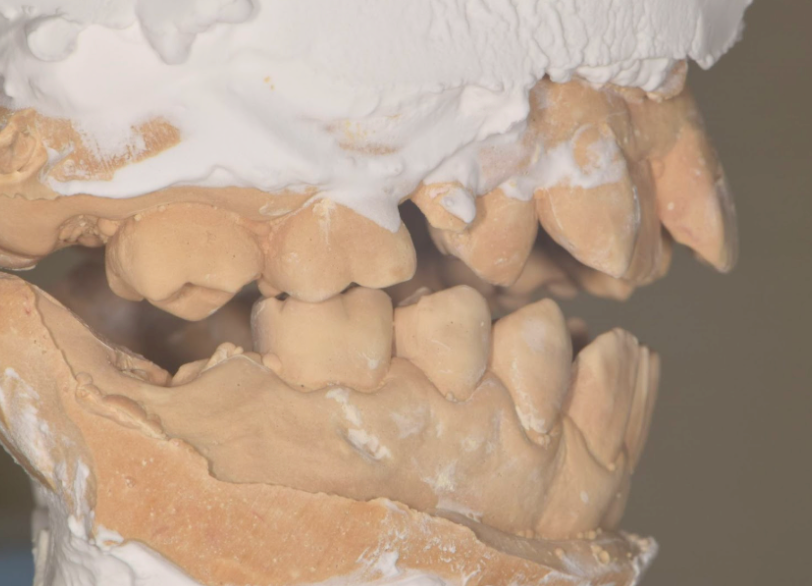

咬合診断模型

咬合診断の結果より現在奥歯でしか歯がかみ合っておらず、どこの歯がどのようにあたっているのか不明確な状態だったため、模型上でどこをどう削れば咬みやすくなるのか、模型上でのシュミレーションを行い必要最小限の介入でかみ合わせの改善を行った。

左の奥歯が一番最初にあたってしまい、口が閉じられない状況が診断で分かったため

下のようにかみ合うように削合を行った。

本来は矯正治療によるかみ合わせの改善が求められるが金銭的な影響から咬合診断で害になるかみ合わせを補正した

左側の歯の削合により右側の咬合を獲得できた